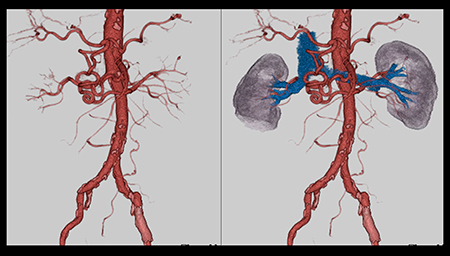

新型X線管VectronはLow kV撮影時でも十分な管電流が出力可能であり,成人の体幹部撮影に十分適用できる。また,腹部大動脈,腎動脈,腎皮質のCT値は,70kVではいずれも120kVの約2倍であり,大きくなったCT値の差を生かすことで,VR画像においても末梢血管を腎内分枝まで明瞭に描出可能である(図1)。

図1 70kVを用いた腎臓のダイナミックスタディ

VR画像